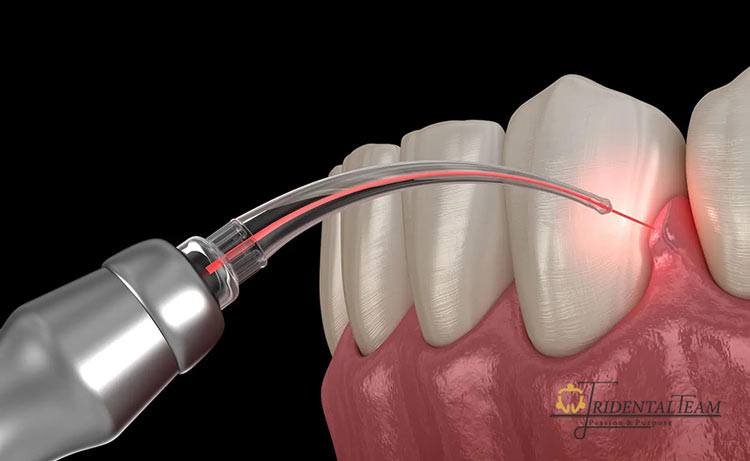

جراحی لثه یا جراحی پریودنتال یکی از روش های درمانی در دندانپزشکی است که برای برطرف کردن مشکلات پیشرفته لثه و بافت های اطراف دندان انجام می شود. این نوع جراحی معمولاً زمانی لازم است که بافت لثه دچار عفونت، التهاب شدید یا تحلیل شده باشد و درمان های ساده تر مثل جرم گیری دندان یا دارو درمانی کافی نباشد. هدف اصلی جراحی لثه، حفظ دندان ها، کاهش التهاب، بازسازی بافت های آسیب دیده و در برخی موارد، بهبود زیبایی خط لثه است.

بر اساس منابع معتبر و علمی دندانپزشکی، جراحی لثه شامل تکنیک های مختلفی مانند لیفت لثه، حذف پاکت های عمیق باکتریایی، یا پیوند لثه می شود که بسته به شرایط دهان بیمار انتخاب می شود. این جراحی به دندانپزشک اجازه می دهد تا به نواحی عمیق تر زیر لثه دسترسی پیدا کند و پلاک، جرم و بافت های بیمار را حذف کند تا زمینه ترمیم طبیعی لثه ها فراهم شود.